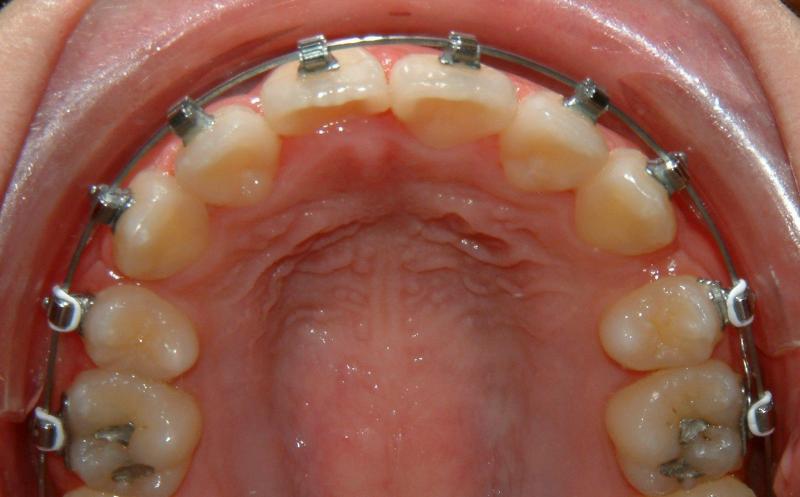

The upper right central incisor and lateral incisor form 2 rows. It would be a fatal mistake to extract either one of these two. It might be the case if the patient has no access to the correct orthodontic treatment. In this case, the 1st premolars are removed. Initial and some progress data are presented in Figs. 1-5.

Fig. 3 The upper 1st premolars are sacrified -- occlusal view